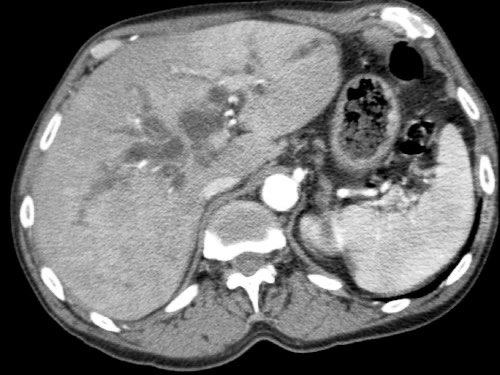

Tái tạo mặt phẳng coronal cho thấy một khối u lớn xuất phát từ cổ tụy với kiểu phát triển xâm lấn (hình A và B).

Có hiện tượng bao quanh động mạch thân tạng 360º (mũi tên trong A).

CT axial MIP tại mức động mạch thân tạng cho thấy hẹp động mạch gan chung bị bao quanh (mũi tên), rất nghi ngờ xâm lấn.